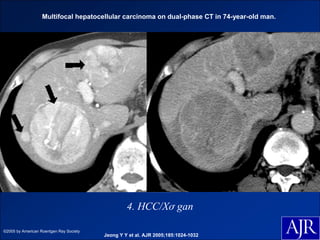

Multifocal hepatocellular carcinoma on dual-phase CT in 74-year-old man.

4. HCC/Xơ gan

©2005 by American Roentgen Ray Society

Jeong Y Y et al. AJR 2005;185:1024-1032